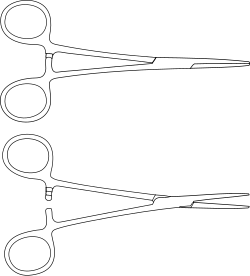

| Kelly forceps |

|

Hemostatic forceps | |

| Kocher forceps |

|

Hemostatic forceps | |